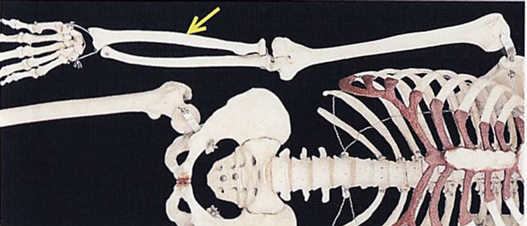

全身骨格前面の一部の写真を別に示す。 矢印で示すのはどれか。1つ選べ。

a. 脛骨

b. 橈骨

c. 腓骨

d. 上腕骨

解答を見る

b